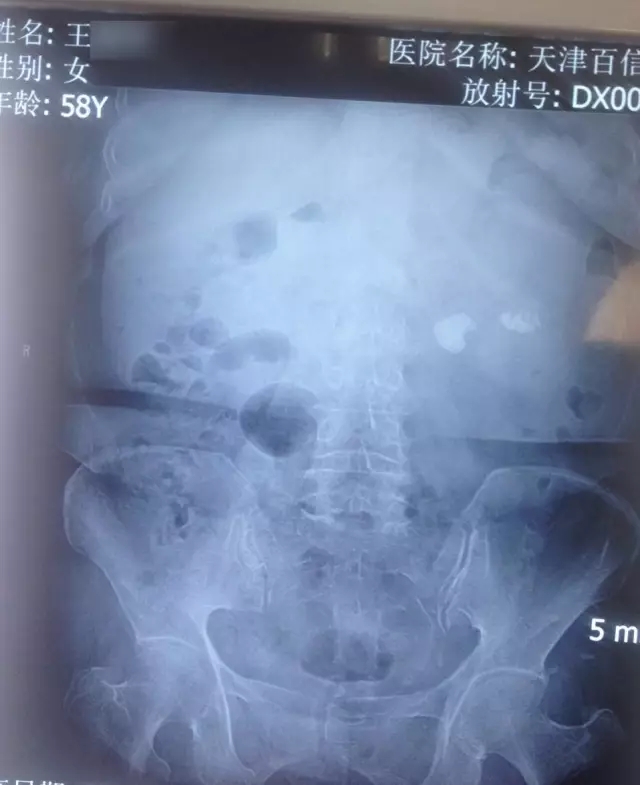

病症表现:患肾结石10年,腹部剧烈疼痛、血尿

诊断结果:左肾结石

其他描述:患者患肾结石10年,曾多次体外碎石,效果不理想,反作。入院检查显示,患者左肾布满大小不一的结石,而且大的直径约1.7厘米位于左肾肾盂输尿管移行处。李月明主任为患者进行经皮肾镜碎石取石术,取出患者左肾内结石,术后检查显示,,接触患者10年困扰。